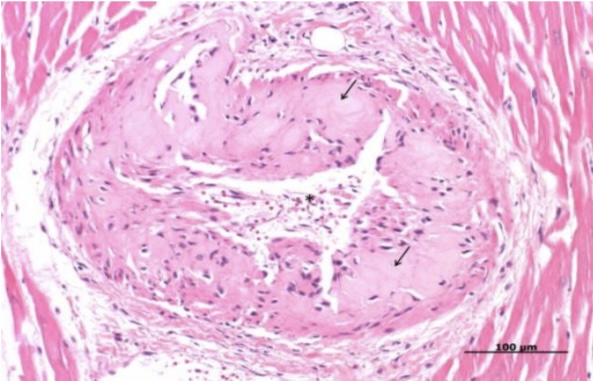

Zenker’s necrosis